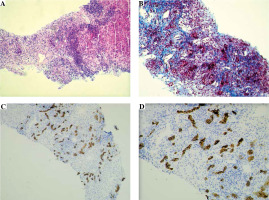

The needle liver biopsy showed a morphological picture of autoimmune liver disease with advanced fibrosis (Batts and Ludwig score 3) corresponding to the AIH/PSC overlap syndrome. Characteristic features for AIH were found, i.e. interface and lobular hepatitis, moderate/severe in nature, with intense portal and periportal lymphoplasmacytic infiltrates and severe necro-inflammatory reaction (Fig. 2A). There was advanced portal, periportal and bridging fibrosis, as well as a significant scar formation covering about half of the biopsy specimen. The process of intense fibrogenesis was accompanied by an abundant amount of mononuclear inflammatory cells in the collagen fibrous tissue (Fig. 2B). Immunohistochemical (IHC) staining of the portal tract for CK7 and CK19 revealed a proliferation of the biliary tree, which morphologically corresponds to small-duct sclerosing cholangitis [3] (Fig. 2C, D).

Fig. 2

Liver histology and immunohistochemistry of tissue material obtained from liver biopsy in a child with ASC. A) Section showing marked chronic portal and periportal intense inflammation in most portal tracts, composed of lymphocytes and plasma cells, with marked interface hepatitis (Mayer’s hematoxylin and eosin – H&E staining, original magnification 100×). B) The view of intense mononuclear infiltrates and expansion of collagen fibers around numerous, proliferating small bile ducts present within the liver scar formation, giving the morphological pattern of small-duct (autoimmune) sclerosing cholangitis (Masson’s trichrome staining, original magnification 200×). Immunohistochemical staining for CK7 well demonstrates the proliferation of numerous bile ductules within the scar formation; abundant mononuclear inflammatory cell infiltrations are present around the neoforming small ducts (IHC, original magnification: 100× (C); 200× (D))